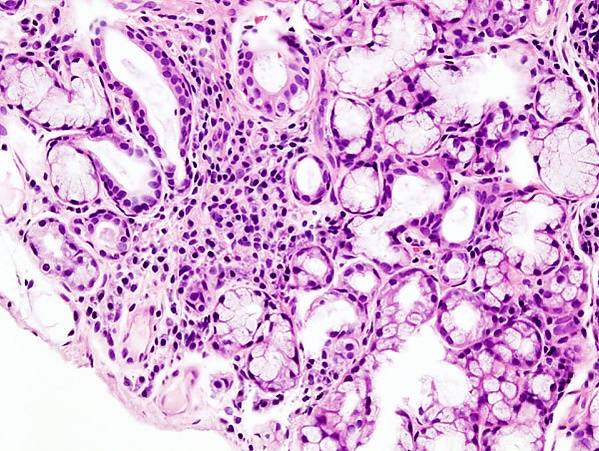

- Биопсия малых слюнных желёз. Обнаруживается инфильтрация слюнных желёз лимфоцитами.